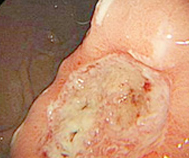

医生简介:王芸凭借其在消化内科领域的杰出贡献,多次受邀出席全国重要学术会议、论坛。为广大患者解除肛肠困扰。对萎缩性胃炎、胃溃疡、十二指肠溃疡等常见疾病具有丰富的诊疗经验...【详细】

• 无痛胃镜

• 无痛肠镜